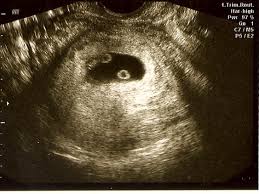

When you re 6 weeks pregnant with twins you are between 5 weeks 0 days and 5 weeks 6 days pregnant. This is when you ll know for sure whether or not your expecting twins. That s also called being 7 weeks pregnant. Twins can be detected on an ultrasound in the first trimester as early as 4 6 weeks after you miss your period and their heartbeats can be found at 6 8 weeks it s also pretty hard to distinguish two heartbeats and having two doesn t always indicate twins.

A twin ultrasound at 6 weeks needs to be done vaginally to detect twins this early in your pregnancy. At this stage it s likely you have an ultrasound. With careful listening a doctor or midwife can sometimes detect multiple distinct heartbeats and might suspect that there are twins. The exact time twins can be detected depends on the type of twins for example if they re identical from one egg or not.

When you re 6 0 weeks pregnant your baby s hearts should be beating and the sonographer should be able to detect them at this point. Researchers estimate that 21 to 30 percent of twins pregnancies result in vanishing twin syndrome. How late can twins be detected. Seeing twins at 6 weeks is definitely possible.